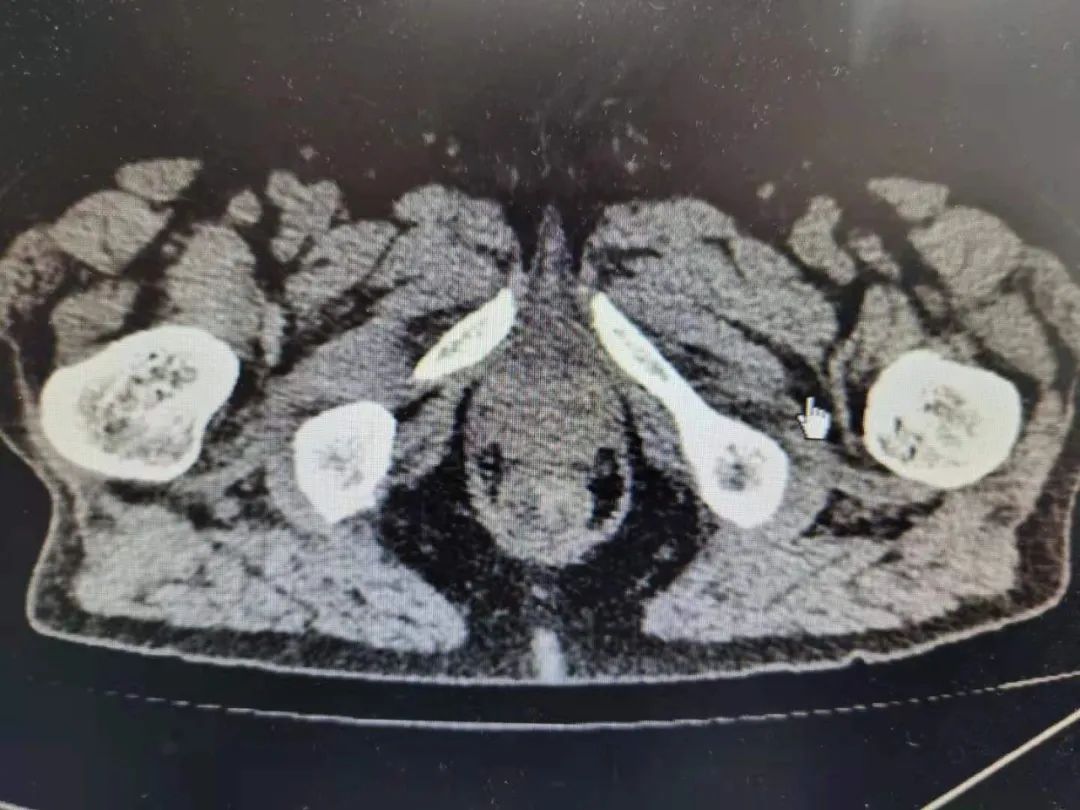

91 岁的吴老先生是高校退休教师,半个多月前他在家人陪同下去医院看诊。吴老告诉医生,自己间断便血已经 1 个多月了。检查确诊为直肠癌,肿块位置极低,距离肛门仅 4 公分。

而且,老人患有糖尿病、阻塞性肺气肿、低蛋白血症、心动过速等多种慢性病,心肺功能极差。姚磊请来心血管内科、呼吸内科、内分泌科、麻醉科等专家综合评估后,决定为吴老先生实施全腹腔镜下极限保肛手术。

棘手的是,吴老先生有近 180 斤体重,BMI 指数达到 28。男性本来骨盆就窄,腹腔镜下手术视野受限,肥胖更是增加了手术难度。在手术室麻醉科的全力支持下,手术最终顺利完成。